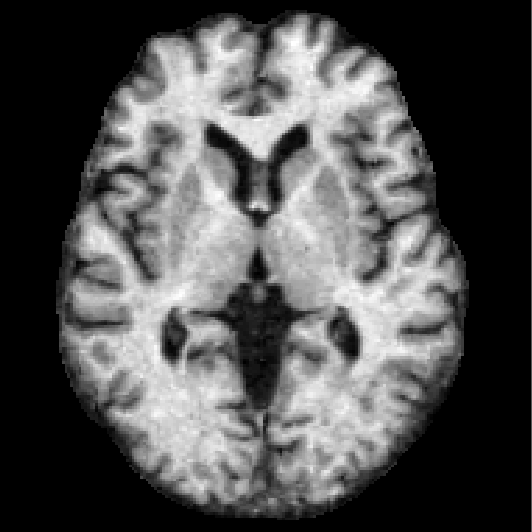

CuRIOUS Hippocampus MR Abdomen CT-CT

Fixed Moving Fixed Moving Fixed Moving

[Uncaptioned image] [Uncaptioned image] [Uncaptioned image] [Uncaptioned image] [Uncaptioned image] [Uncaptioned image]

Modalities MR T1w & FLAIR/US MR T1w/MR T1w CT/CT

Intra-/Inter-patient Intra-patient Inter-patient Inter-patient

Resolution 256×256×288256256288256{\times}256{\times}288 64×64×6464646464{\times}64{\times}64 192×160×256192160256192{\times}160{\times}256

Voxel size 0.5×0.5×0.5 mmsimilar-toabsent0.50.50.5timesabsentmillimeter{\sim}0.5{\times}0.5{\times}0.5$\text{\,}\mathrm{mm}$ 1×1×1 mm111timesabsentmillimeter1{\times}1{\times}1$\text{\,}\mathrm{mm}$ 2×2×2 mm222timesabsentmillimeter2{\times}2{\times}2$\text{\,}\mathrm{mm}$

Cases (Train/Test) 22/10 263/131 30/20

Preprocessing resample crop/pad/resample canonical affine pre-align

crop/pad/resample

Annotations (Train/Test) –/9-18 landmarks/case 2/2 anatomical labels 13/13 anatomical labels

Additional data

Metrics TRE/TRE30 DSC/DSC30/HD95 DSC/DSC30/HD95

SDlogJ/RT SDlogJ/RT SDlogJ/RT

TABLE I: Overview of all six Learn2Reg tasks addressing the imminent challenges of medical image registration: multi-modal scans \mathbin{\vbox{\hbox{\scalebox{2.0}{$\bullet$}}}} (tasks with at least two different image modalities), few/noisy annotations \mathbin{\vbox{\hbox{\scalebox{2.0}{$\bullet$}}}} (less than five annotated anatomical structures for training cases), partial visibility \mathbin{\vbox{\hbox{\scalebox{2.0}{$\bullet$}}}} (restricted or cropped field of view for at least one image of a registration pair), small datasets \mathbin{\vbox{\hbox{\scalebox{2.0}{$\bullet$}}}} (less than 30 training cases), large deformations \mathbin{\vbox{\hbox{\scalebox{2.0}{$\bullet$}}}} (tasks with initial displacements of at least 10 cm10timesabsentcentimeter10$\text{\,}\mathrm{cm}$), small structures \mathbin{\vbox{\hbox{\scalebox{2.0}{$\bullet$}}}} (tasks containing cases with target structures comprising less than 100 voxels), unsupervised registration \mathbin{\vbox{\hbox{\scalebox{2.0}{$\bullet$}}}} (no annotations for training cases) and missing correspondences \mathbin{\vbox{\hbox{\scalebox{2.0}{$\bullet$}}}} (e.g. due to removed organs, different field of views etc.)

.

OASIS

The task employed 416 3D whole-brain MR scans from the Open access series of imaging studies (OASIS) [30], a cross-sectional MR data study with a wide range of participants from young, middle-aged, nondemented, and demented older adults. The clinical relevance of this inter-patient registration task lies in quantitative brain analysis, which is of utmost importance for a better understanding of the human brain and for the analysis of various brain diseases. Standard brain MR pre-processing including skull-stripping (optional), normalisation, pre-alignment, and resampling was performed. Semi-automatic labels with manual corrections of 35 cortical and subcortical brain structures were generated using FreeSurfer [31]. For details on data curation, see [32].